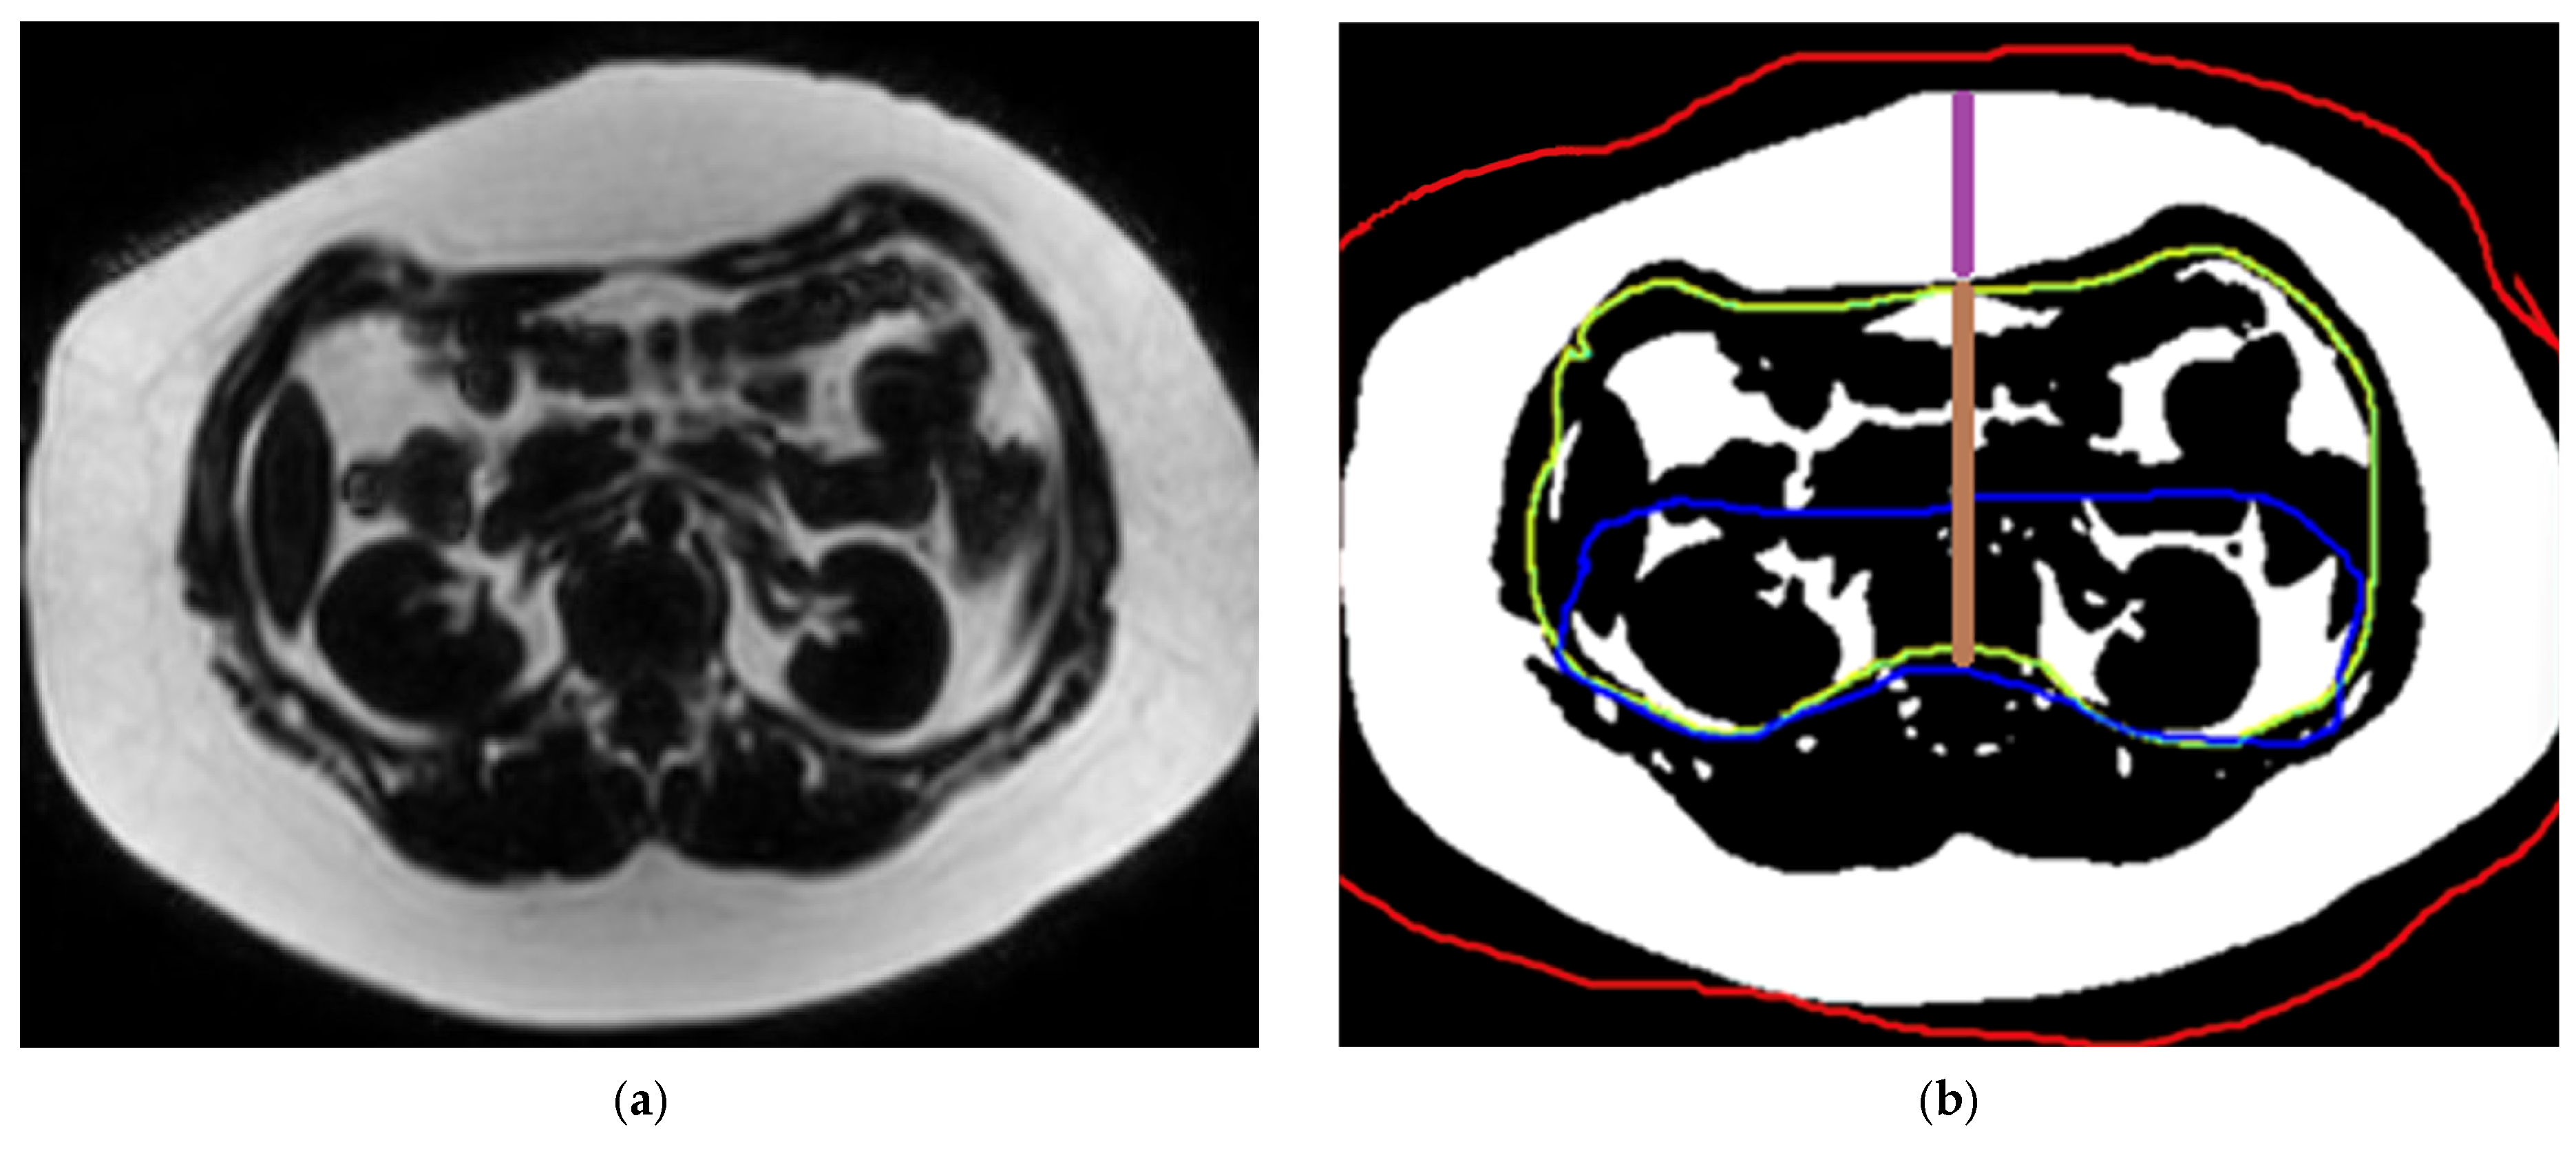

2.3.3. Measurement of Abdominal Fat Compartment Surface Area and Thickness